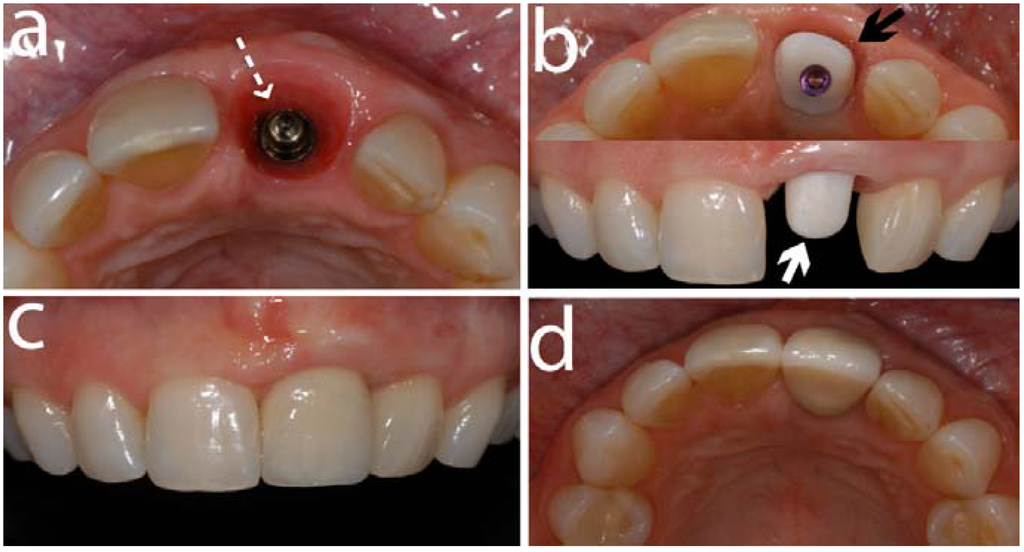

Figure 6.

This sequence of clinical images shows a titanium implant (Straumann, Basel, Switzerland) placed (a) in a left central incisor area (segmented white arrow). (b) illustrates the occlusal view (black solid arrow) and front view (white solid arrow) of a zirconia abutment (Cares Abutment, Straumann, Basel, Switzerland) screw-retained on the implant. (c) and (d) are front and occlusal views respectively of the final restoration cemented on the abutment.

5. Zirconia Abutments for Oral Implants

So far, only one randomized controlled clinical trial comparing zirconia and titanium abutments supported by 40 single implants was published [81]. After being in function for three years, 18 zirconia and 10 titanium abutments were followed-up. Both abutment materials exhibited survival rates of 100%, as well as similar biological and esthetical outcomes.

Based on the results of an in vivo study, zirconia abutments showed resistance to high loads of up to 738 N [84]. These loads exceed the ones occurring at implants in anterior regions, being in a range of 370 N [85].